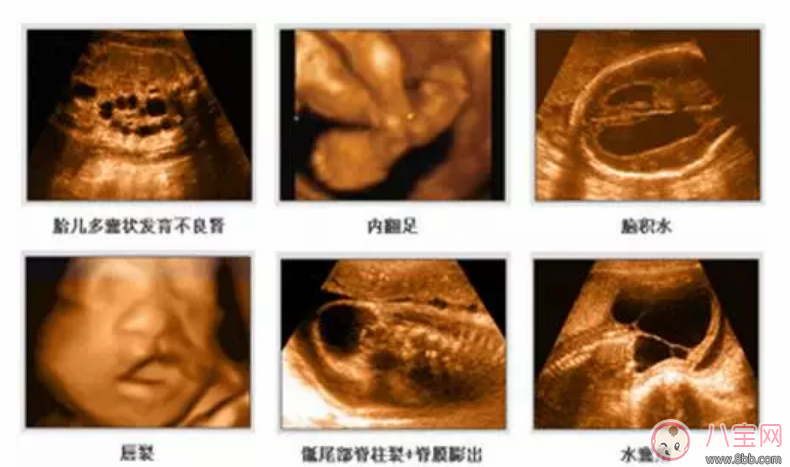

2、四維彩超能多方位,多角度地診斷胎兒各器官的發(fā)育情況,可以精確篩查先天性畸形,例如骨骼發(fā)育異常、唇裂等癥狀,有利于胎兒早期診斷治療。

3、四維彩超能對胎兒的體表進(jìn)行檢查,能夠準(zhǔn)確、清晰檢測出胎兒發(fā)育是否異常,及早檢查胎兒的大腦、脊柱、骨骼、面部是否有發(fā)育不良的情況,以便盡早的進(jìn)行治療。